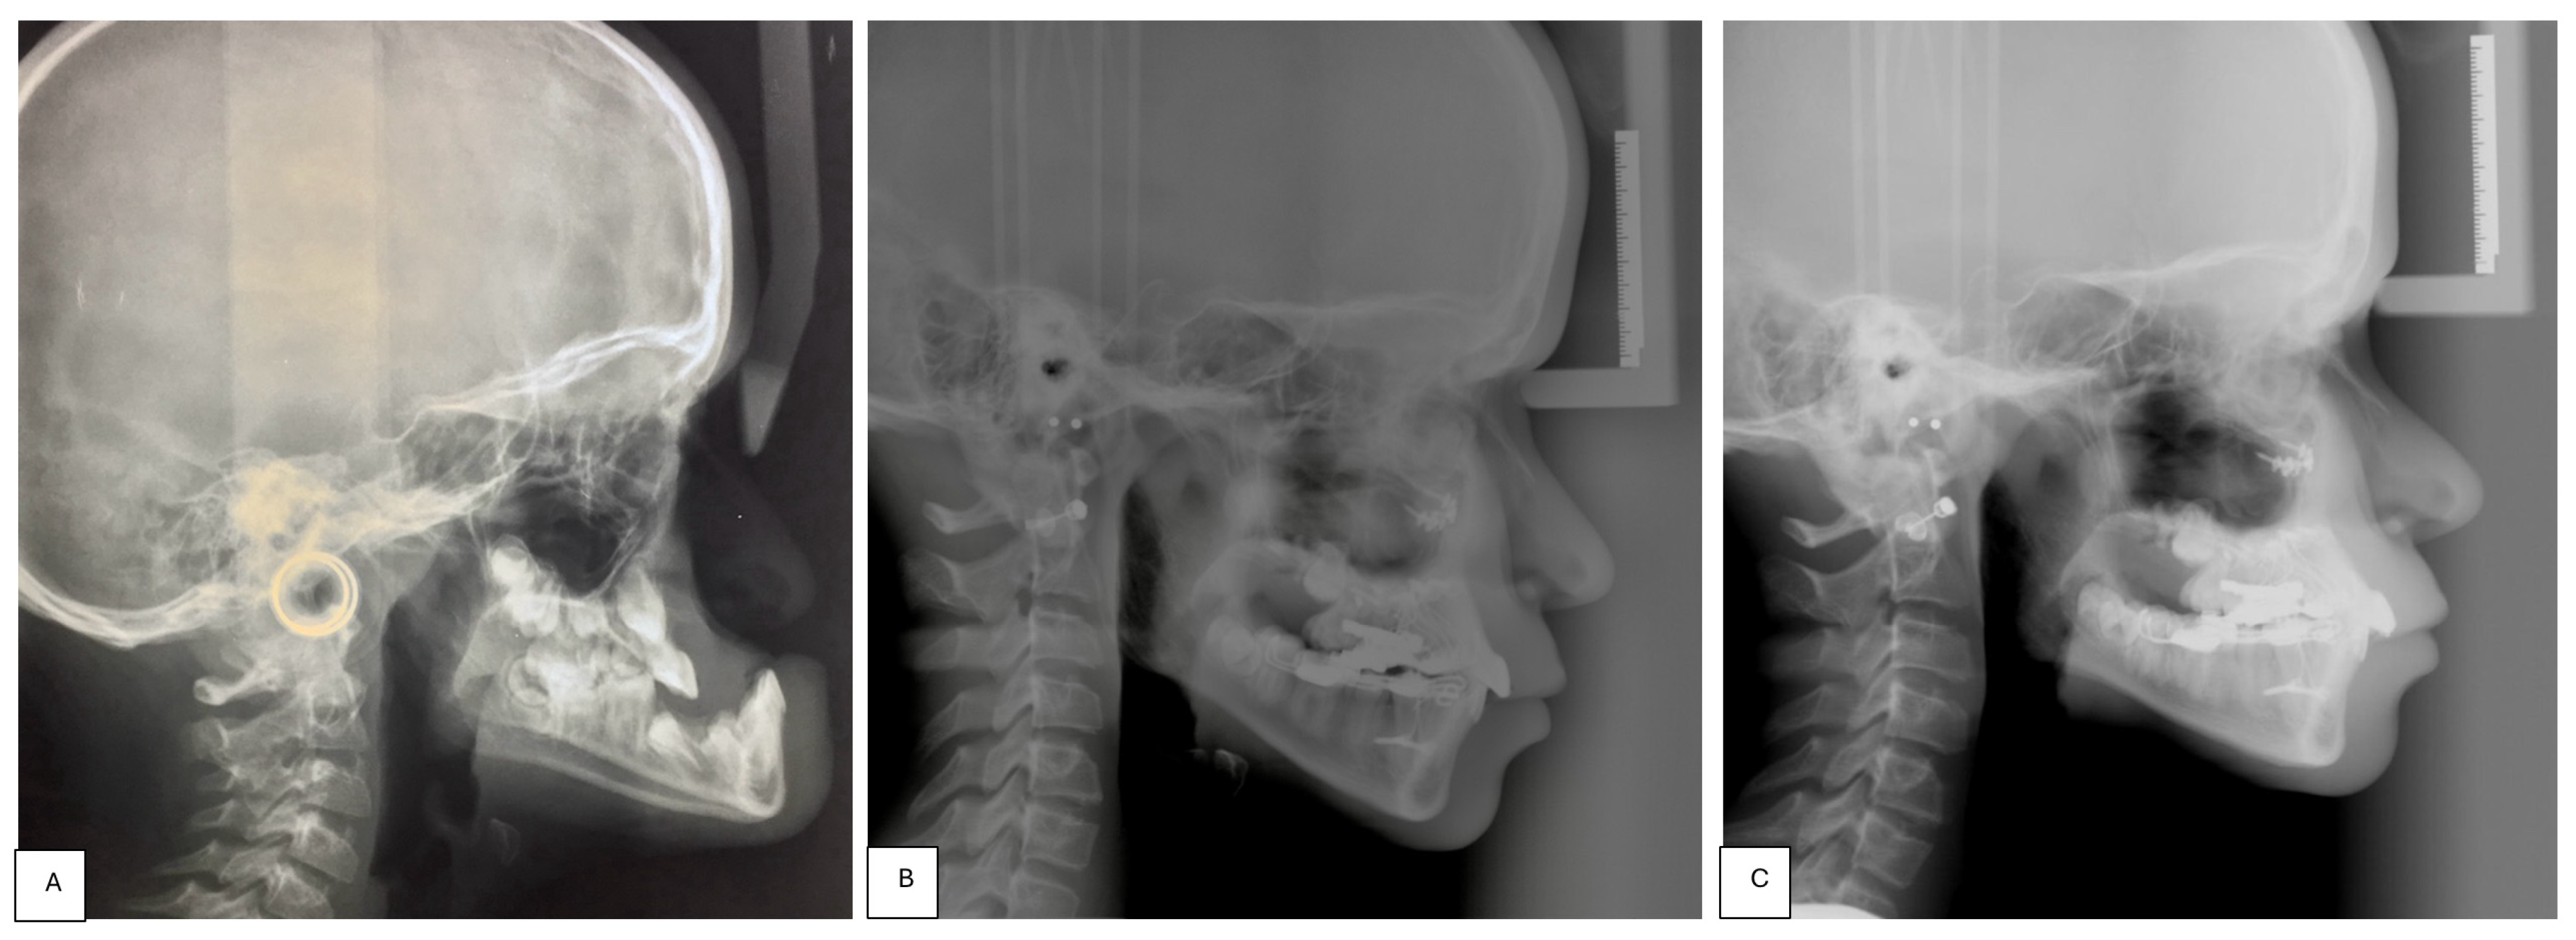

- Placement of an external rigid distractor (RED) during a minor surgery under general anesthesia. The surgical procedure was performed with oro-tracheal intubation through an incision at the level of the upper vestibular fornix with skeletonization of the maxilla. The patency of the zygomatico-maxillary suture was noted. A plate and corresponding screws (Matrix Midface, DePuy Synthes, Raynham, MA, USA) were positioned on each side at the level of the maxillo-malar complex, and two plates, corresponding screws, and percutaneous pins (External Midface Distractor, DePuy Synthes, Raynham, MA, USA) were placed at the level of the lower orbital rim. Percutaneous traction wires were secured to the inferior plates and left protruding at the level of the naso-labial fold. After all intraoral wounds were sutured, the halo was positioned using four cranial screws per side (External Midface Distractor, DePuy Synthes, Raynham, MA, USA). The immediate post-operative period was organized in the Pediatric Intensive Care Unit. As ongoing NIV therapy was critical, the tractions of the RED were positioned in such a way as not to impede the placement of the NIV interface during night (Figure 5).

- Activation of the RED to allow advancement of the midface to overcorrect the dysmorphism. The activation started the day after surgery, 0.5 mm per day. After 4 weeks, the dislodgement of a bone anchorage plate was observed, necessitating an additional intervention to reposition it with a modification of its geometry. The activation continued for 5 additional weeks, for a total of 9 weeks, with an advancement reaching approximately 20 mm at the maxillary level.

- At the end of the distraction phase, after an additional stabilization period of 4 weeks, the RED was removed.

- Continuation of orthopedic–orthodontic treatment for approximately 9 months using intra-oral traction elastics, following the placement of orthodontic anchorage screws in the jaws under local anesthesia.